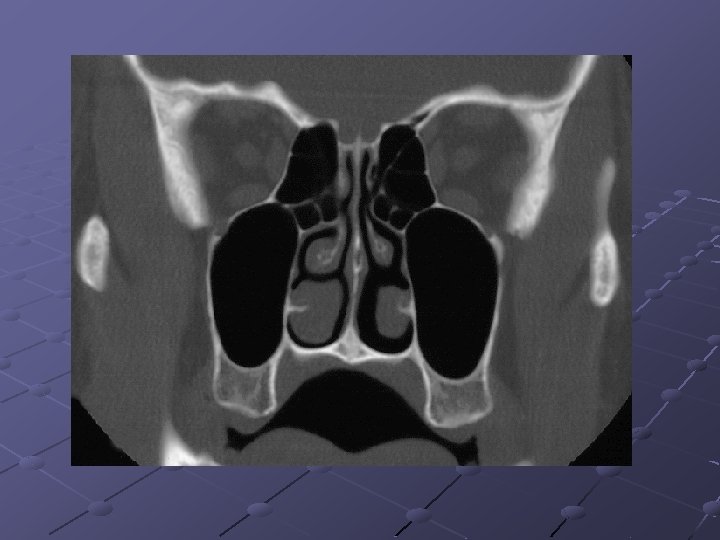

CRS 78 had criteria to CRS 17 endoscopy: positive 37 - CT findings: positive 6 endoscopy : positive 41 - CT findings: negative 35: endoscopy negative & CT negative 20: endoscopy negative & CT positive 55: endoscopy negative Stankiewicz & Chow: Otolaryngol Head Neck Surg 2002

Radiology & clinical exam Correlated with a Sensitivity of 75% And specificity of 84% Endoscopy correlated poorly with sinus disease and not predictive Stankiewicz & Chow: Otolaryngol Head Neck Surg 2002

Endoscopy/ct findings/clinical Easy to diagnose CRS by endoscopy alone when nasal polyps, purulence, or fungus is observed, when absent, establishing the diagnosis may be more difficult 45% of patients with clinical CRS were both endoscopically and radiographically negative. Stankiewicz and Chow. Otolaryngol head neck surg 2002

Endoscopy/ct findings/clinical Negative endoscopy alone is insufficient to rule out sinusitis. 26% of patients who were negative on endoscopy had positive CT – this would suggest that if endoscopy is negative most of the time the ct will be also negative, even with a positive history. Stankiewicz & Chow: Otolaryngol Head Neck Surg 2002

The surgical site in children There is strong evidence to support the fact that the OMC area is the primary site of involvement of inflammatory sinuses disease.